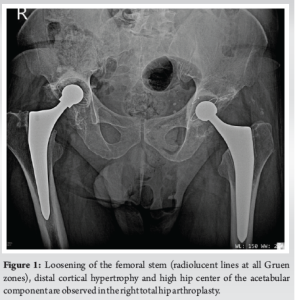

A 64-year-old male patient presented to the orthopedic outpatient department complaining of painful right THA during his everyday activities and severe limping. The indication for the primary THA was end-stage primary hip osteoarthritis and it was performed 7 years ago through the modified Hardinge’s approach. The past medical history included benign prostatic hyperplasia. The clinical evaluation revealed approximately 2.5 cm leg-length discrepancy and at the standard pre-operative radiological evaluation it was identified loosening of the right femoral stem since radiolucent lines around the stem, anterior thigh pain, and varus malalignment were evident. The pre-operative work-up was negative for infection, and aseptic loosening was considered the final diagnosis. The severe leg-length discrepancy and the high hip center were the two main reasons for the revision of the acetabular component. A modified Hardinge’s approach was performed. After the removal of the acetabular and femoral components, a thorough debridement of the acetabular bone bed and the femoral canal was performed until sufficient bleeding was evident. The femoral bone defect was classified as type I whereas the acetabular bone defect was classified as type IIIA according to Paprosky classification (type III according to Saleh classification) [20,21] (Fig. 1). Moreover, intra-operative tissue samples were collected and sent for microbiological cultures which were finally negative. The acetabular bone defect was addressed with a cup-cage construct in conjunction with the impaction of morselized allograft (fresh-frozen femoral head). The ischial hook was placed at the obturator foramen and the iliac flanges were adjusted accordingly to the iliac bone and stabilized with five screws. The femoral component was revised using a type 3 (trochanteric sparing) short stem since there was sufficient bone stock and of good quality the proximal femur. Before the placement of the final components, an intra-operative fluoroscopic image was obtained to confirm the correct sizes and position of the implants.